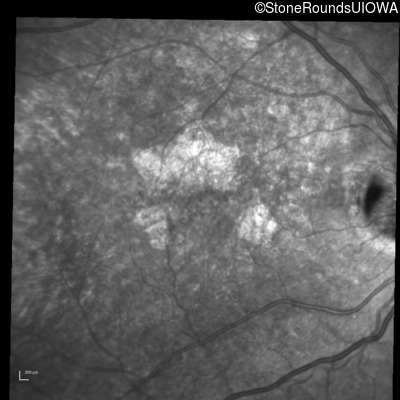

Blue Autofluorescence - Right - 20/32 +2

Exemplar